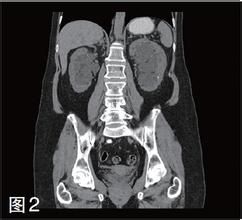

(1)B超和CT 靈敏度取決於囊腫大小,它們均不能發現太小的囊腫。

臨床表現如兩側腎臟明顯增大、尿異常、高血壓等應懷疑有本病的可能,如有家族史則更能提示本病。B超、CT檢查能發現特徵性雙腎囊腫,診斷即可確立。本病早期腎囊腫數目不多,可為單側性,數年內複查如腎囊腫數量增多或出現腎外囊腫,診斷也可肯定。套用基因連鎖分析法診斷囊腫基因極為可靠。如果不能做基因連鎖分析,多囊肝,顱內動脈瘤,胰腺囊腫和腎功能不全均有助於輔助診斷。